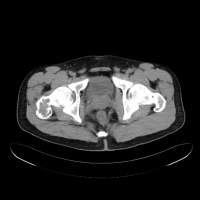

二CT:

1.骨囊肿一般多呈圆形、卵圆形低密度骨质缺损,边缘清晰,无硬化。

2.局部骨皮质变薄呈囊性膨胀。

3.少数囊肿内可见骨性间隔,呈多房改变。

4.骨囊肿内的CT值多为水样密度,有出血时密度可升高。

5.增强扫描囊肿不强化。